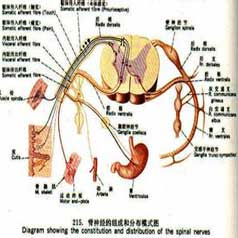

带状疱疹病毒性睑皮炎

疾病介绍:本病是由带状疱疹病毒感染三叉神经半月神经节或三叉神经第一支所致,多见于老年人或体弱者。多有发热、乏力、全身不适的前驱症状。随后病变区出现剧烈…【详细】